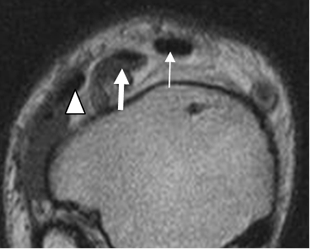

Fig 17. Ligamento calcaneoescafoideo.

A: RM axial en T1 y B: RM sagital en T2. Ligamento hipointenso normal, entre el escafoides y el calcáneo.